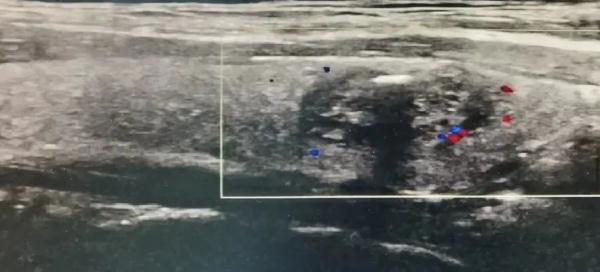

今年,小丽在入职体检时发现结节变大了。B超提示,结节大小1.2cm,形态不规则,直立状,内见沙粒样钙化,可见短棒状血流。

两年没复查,小丽的甲状腺结节恶化了,医生考虑甲状腺恶性肿瘤的可能性大。小丽这才害怕了,来到杭州师范大学附属医院甲乳外科就诊。经过超声引导下的精准甲状腺结节细针穿刺、颈部增强CT等检查后,主任医师孟柠明确小丽得的是甲状腺乳头状癌。